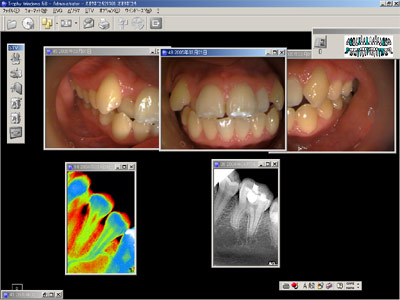

革新的なデジタルX線画像解析システム(compuray)を使用し正確な診断治療を行っています。

この利点は、X線照射量がふつうのレントゲンに比べて約1・10で済むことです。

フィルムと違い、拡大や画像解析がモニター上で、容易に行えること。フィルムの現像液や定着液などの廃液の心配がないこと。妊婦やお子さんにも安心していただけます。

この装置ではフィルムの代わりに高感度CCDセンサーを使用しているため体にやさしい装置なのです。

またレントゲンの画像をリアルタイムにデジタル画像としてモニターに表示するという、装置なのです。